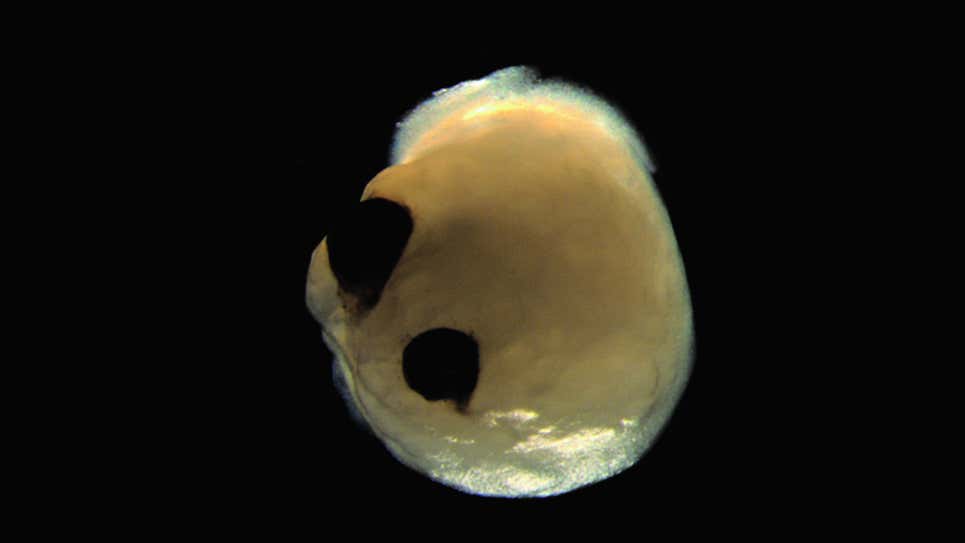

Ahora las células madre presumen de ojos. Un equipo internacional de investigadores dice que ha desarrollado una masa de tejido cultivada en laboratorio que imita un cerebro y que fue capaz de producir espontáneamente dos copas ópticas simétricas, estructuras similares a ojos sensibles a la luz. Pero no te preocupes, estos organoides rudimentarios no son conscientes.

El primer día de la investigación del equipo, las células madre eran un montón de puntos desconectados. El día 10, habían formado una neuroesfera, un grupo de tejido celular. Hacia el final del primer mes, ya se había formado el organoide con un campo ocular primitivo, un grupo de células retinianas que son el primer plano de estructuras oculares más complejas. A los dos meses, se habían formado vesículas ópticas completas, que son la base de los ojos y están conectadas al cerebro.

Un poco más del 70% de los organoides cerebrales que generó el equipo formaron copas ópticas y las estructuras formaron redes de neuronas eléctricamente activas que eran sensibles a la luz. Las copas ópticas de los organoides también tenían lentes y células corneales.